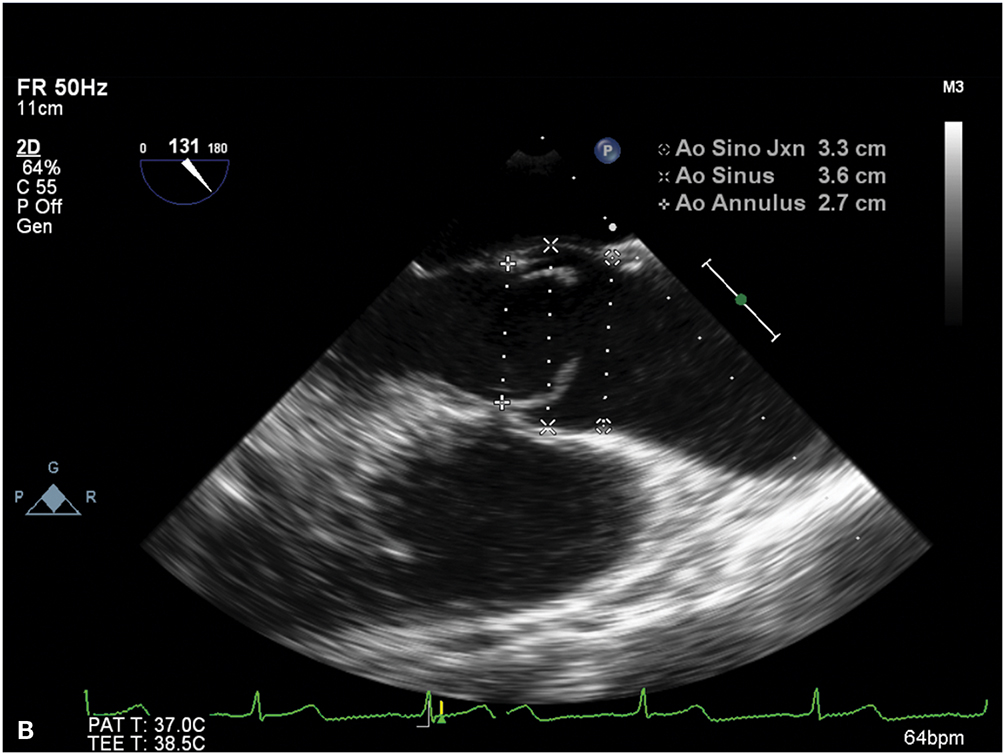

Figure 9.5.: A. Midesophageal Aortic Valve (Av) Short-Axis View on Transesophageal Echocardiography Showing a Bicuspid Valve, with the Fusion of the Left and Right Coronary Cusps.

A. Midesophageal aortic valve (AV) short-axis view on transesophageal echocardiography showing a bicuspid valve, with the fusion of the left and right coronary cusps. B. Midesophageal aortic valve long-axis view on transesophageal echocardiography demonstrating the characteristic doming of a stenotic bicuspid AV and blunting of the sinotubular junction due to aortic root (ascending aortic) dilatation.